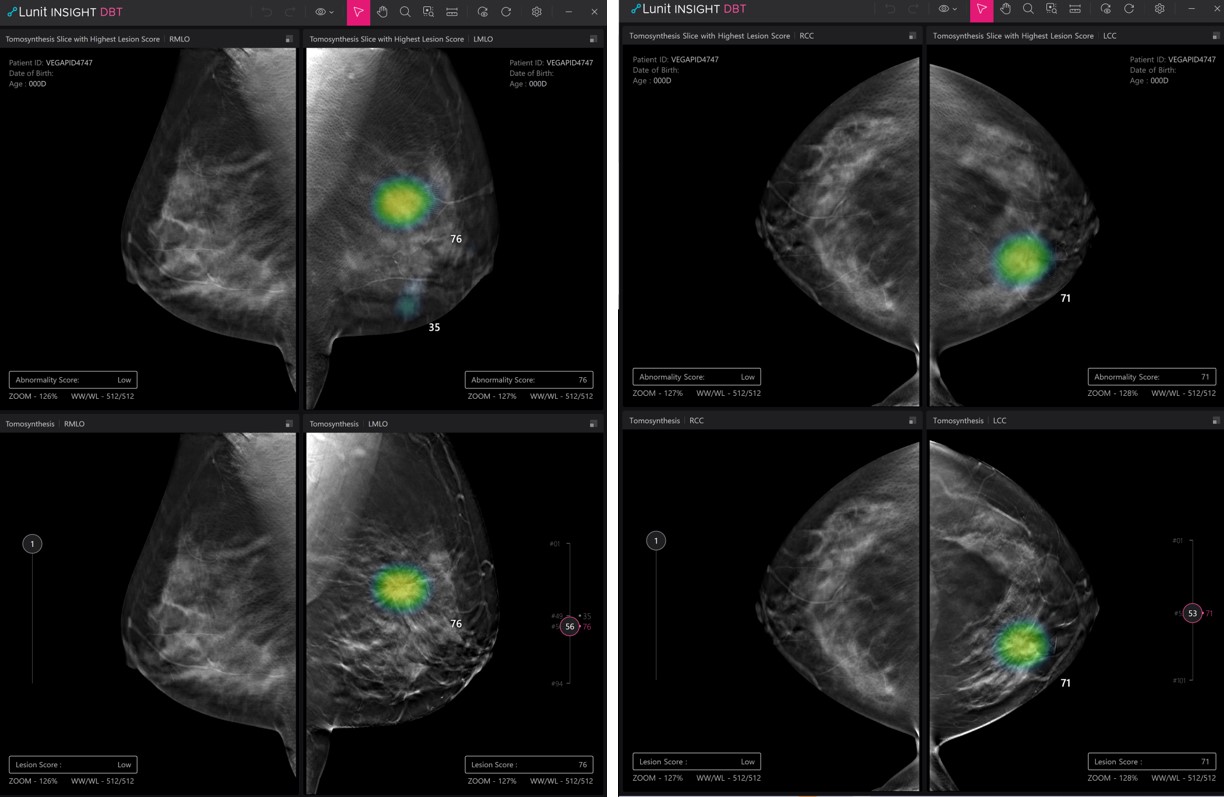

Among the 13 abstracts, three are on Lunit’s newly developed AI solution for digital breast tomosynthesis (DBT), which is the three-dimensional version of the conventional two-dimensional mammography test, rapidly becoming the main screening modality for breast cancer. In the highlight abstract selected to be presented orally, Lunit INSIGHT DBT was demonstrated to have very high accuracy, with an area under the curve (AUC) of 0.943 and sensitivity and specificity of 84.5% and 91.6%, respectively.

Demo image of Lunit INSIGHT DBT

“This is the first time to showcase Lunit INSIGHT DBT in RSNA and we are glad to present meaningful results as the official launch is on its way,” said Ki Hwan Kim, Chief Medical Officer of Lunit. “Through many years of internal validation, we believe the AI algorithm using a large dataset of DBT can improve breast cancer detection and has the potential to show consistent performance across different patient populations and mammography vendors.”